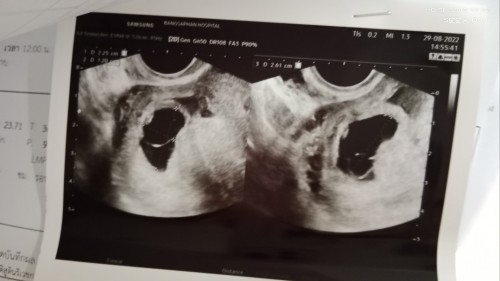

แชร์ประสบการณ์ท้องลมค่ะ แม่ตรวจเจอ2ขีดชัดมากตอน6week เพราะมีอาการแพ้หนักมากคัดเต้ากินไม่ได้อาเจียนตลอดเวลาเหม็นทุกอย่างใจสั่นตลอด ไปฝากครรภ์ตอน8week หมอแค่ถามรอบเดือนล่าสุดและให้ยาบำรุงมากินแม่ได้บอกหมอแล้วว่ามีเจ็บท้องน้อยนนิดๆหน่วงๆแต่ไม่มีเลือดออกหมอบอกเพราะมดลูกขยาย 9+2week2นัดไปซาวทางหน้าท้องก็ไม่เจอเจอแต่ถุงตั้งครรภ์2เซนหมอบอกอาจท้องลม แม่ก็ยังงงเพราะไม่เคยได้ยิน นัดอีกตอน10weekซาวทางช่องคลอดก็ยังไม่เจอสรุปท้องลม ได้นอนรพ.วันนั้นเลยเช้าวันต่อมาได้ดูดออก ครบ5เดือนแล้วนะที่จิ๋วไม่อยู่เมื่อไหร่จะกลับมาหาแม่อีกนะเฝ้ารอทุกวัน